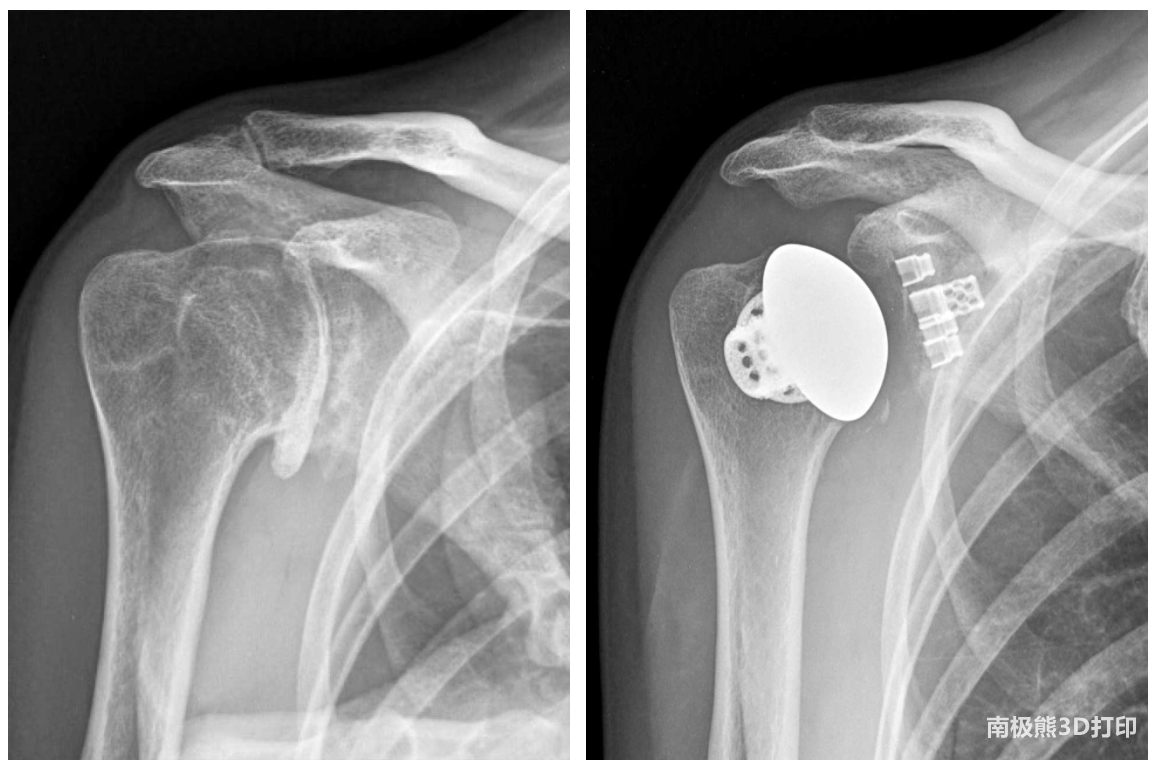

术前X光片(左)和术后X光片(右)显示了激光打印的Stemless Shoulder和Equinoxe Cage Glenoid (图片由Stephanie Muh提供)